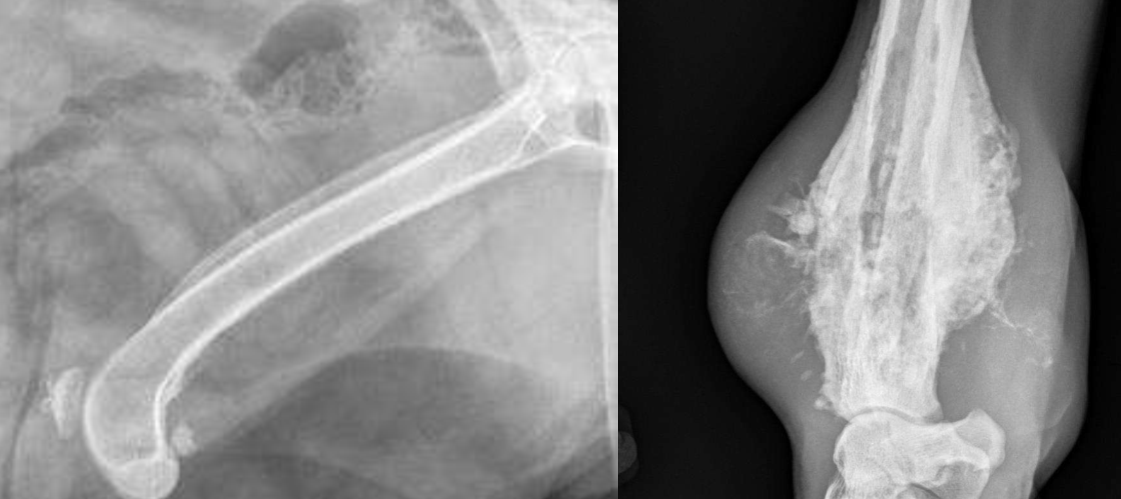

Soft tissue mineralization of the triceps at its insertion on the tuber olecrani

dystrophic

Soft tissue mineralization caudal to the ulna

Soft tissue mineralization at the area of the gastrocnemius

Could be healing from a wound, or a lymph node. Maybe dystrophic?